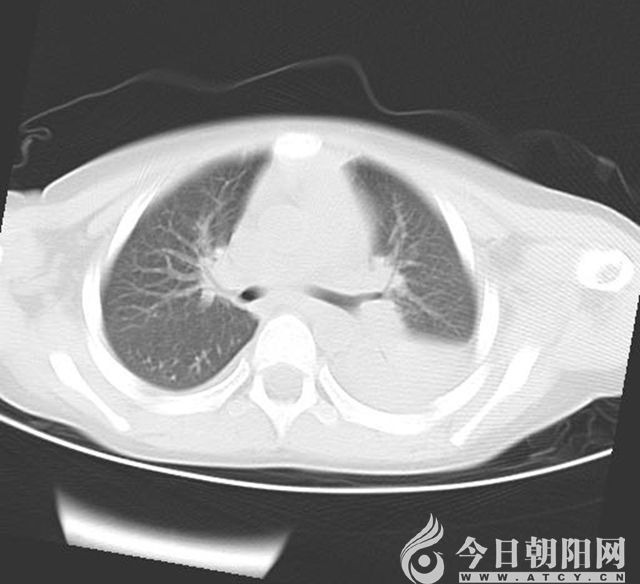

做鏡6天后復(fù)查肺CT

7月5日,一名4歲大的男孩兒,因“發(fā)熱7天,咳嗽3天”來到朝陽市第二醫(yī)院兒科就診。入院時,患兒精神狀態(tài)差,呻吟,無鼻翼扇動,可見輕度三凹征,左肺呼吸音較右側(cè)減弱;肺CT顯示左肺炎性病變,左肺下葉膨脹不良。通過檢查,診斷為重癥肺炎、胸腔積液、膿毒血癥、支原體感染,給予4代抗生素抗感染及抗支原體治療。住院第5天,復(fù)查肺CT顯示左肺下葉膨脹不良無明顯改善,考慮存在痰栓堵塞,立即進行纖維支氣管鏡檢查+支氣管肺泡灌洗術(shù)治療,灌洗過程中吸出塑形性痰栓多量。術(shù)后第6天復(fù)査肺CT,左肺上葉片影消失,左肺下葉膨脹不良明顯改善。7月19日,患兒出院。7月末,男孩兒來到醫(yī)院復(fù)査,肺CT顯示炎癥基本吸收。